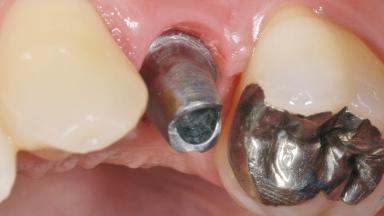

In 2004, a 36-year-old male patient, a non-smoker, presented due to acute pain in the premolar region of the upper left jaw. An orthopantomograph revealed that tooth 24 had been endodontically treated. It also became evident that, during root-canal filling,endodontic filling material had been pushed beyond the apex. This material was located very close to the maxillary sinus floor. Due to this finding in combination with the severe pain and a possible root fracture, tooth 24 was extracted. The esthetic expectations of the patient were not too high and his individual esthetic risk profile summed up to a medium risk profile.

Type of Implants One-Piece

Attachment One-Piece

Abutment Type Customized

Prosthesis Type FDP